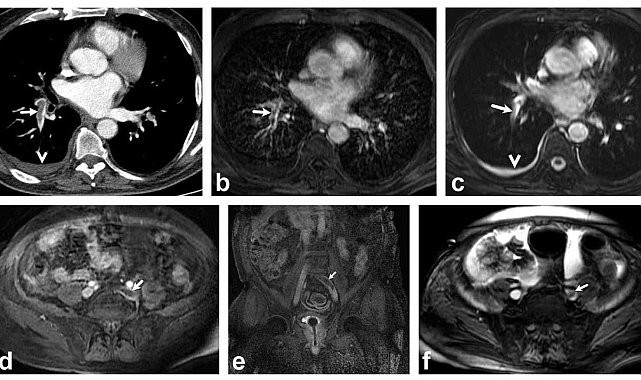

Bir dönem Denizli Tekden Hastanesinde de çalışan ve çalışmalarına ABD'de devam Dr. Nevzat Karabulut ve ekibinin yaptığı, British Journal of Radiology dergisinde yayımlanan "Diagnostic performance of contrast-enhanced and unenhanced combined pulmonary artery MRI and magnetic resonance venography techniques in the diagnosis of venous thromboembolism" başlıklı araştırmada manyetik rezonans (MR) yöntemi kullanılarak hem akciğer damarlarının hem de pıhtının kaynağı olan bacak toplardamarlarının aynı anda, tek bir incelemede değerlendirilebileceği gösterildi. Toplam 44 hastanın incelendiği çalışmada elde edilen sonuçlar oldukça dikkat çekti.

Kontrastlı MR yöntemi, hastaların tamamında akciğer embolisini doğru şekilde tespit ederken; kontrastsız MR yöntemi de yüksek doğruluk oranına ulaştı ve önemli ölçüde güvenilir sonuçlar verdi. Bu bulgular, radyasyon içermeyen MR yönteminin pıhtı hastalığını saptamada güçlü bir alternatif olduğunu ortaya koydu. Özellikle Radyasyon riskinin daha önemli olduğugenç hastalarda ve gebelerde MR'ın güvenli ve etkili bir seçenek olabileceği vurgulandı.